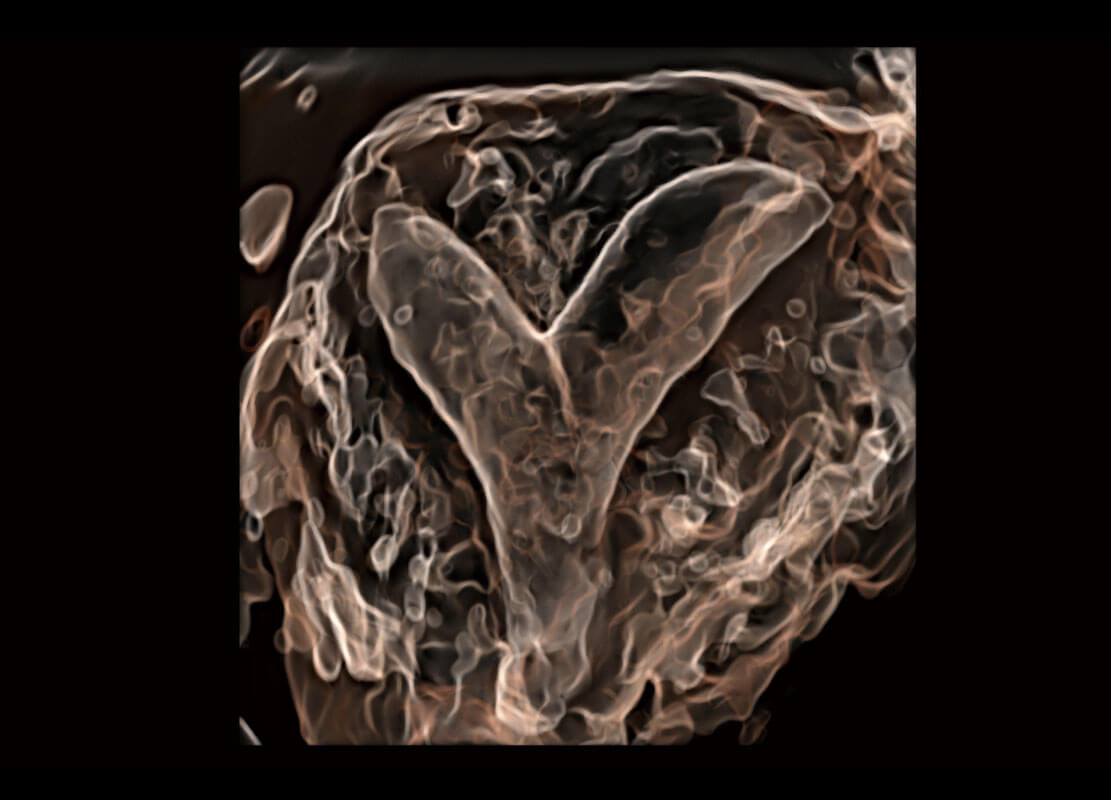

胎心筛查

P60搭载一系列胎儿心脏成像技术,实现精细的胎儿心脏评估。

• 右室双出口

• 胎心容积成像